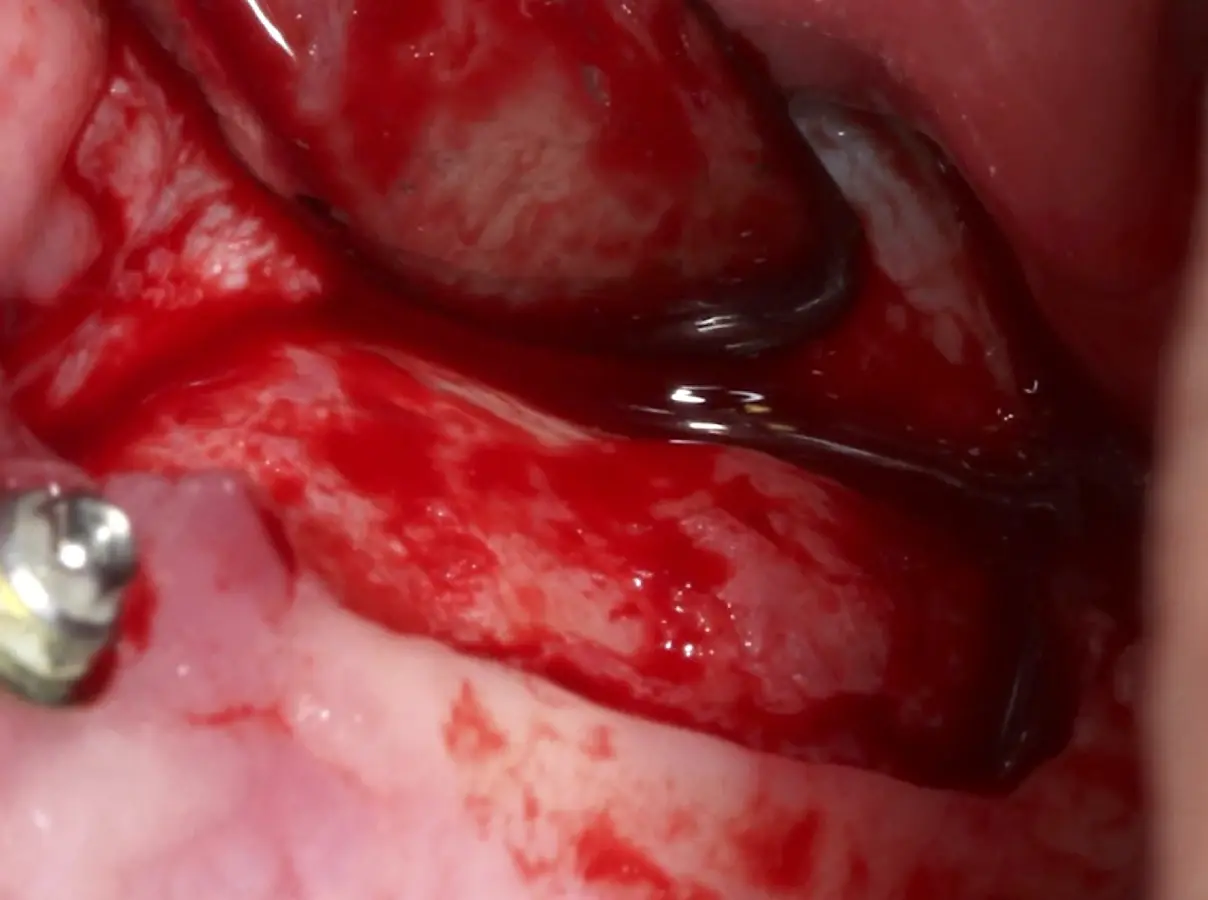

El tipo de inserto a ser utilizado dependerá del espesor de la pared ósea. Si la pared es menor a 0.5 mm, es mejor utilizar insertos de desgaste para prevenir la ruptura de la membrana de Schneider; si el espesor es mayor a 0.5 mm, se puede utilizar insertos de corte de espesor medio (Figura 3).

Figura 3. Osteotomía por desgaste con inserto redondo de punta diamantada (a). Osteotomía por desgaste con inserto plano de punta diamantada (b). Osteotomía por corte con inserto plano de punta aserrada (c).